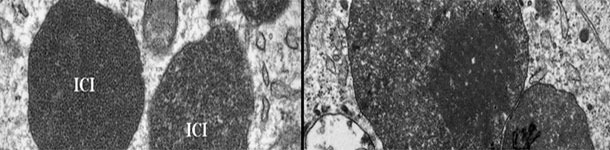

Este artículo explica los factores a tener en cuenta para determinar el momento óptimo de la vacunación frente a PCV2 y muestra los resultados de un estudio que valora la eficacia de distintos programas vacunales en una granja con infección subclínica.

El PCV2 se ha ido asociando cada vez a más patologías, denominadas colectivamente enfermedades asociadas a PCV2 (PCVDs), como ES-PCV2, EP-PCV2, EE-PCV2, ER-PCV2, IS-PCV2 y SDNP.

Novedades sobre las vías de excreción, rutas de transmisión, factores de riesgo, etc y la explicación de porqué PCV2 se convierte en un virus patógeno.

La forma más eficaz de evitar pérdidas productivas asociadas a PCV2 es evitar que se produzca la viremia, induciendo una inmunidad pasiva o activa que minimice la circulación del virus en la granja.